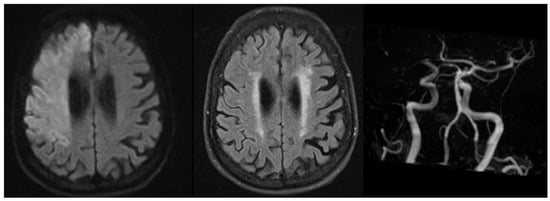

- Roaldsen, M.B.; Eltoft, A.; Wilsgaard, T.; Christensen, H.; Engelter, S.T.; Indredavik, B.; Jatužis, D.; Karelis, G.; Kõrv, J.; Lundström, E.; et al. Safety and efficacy of tenecteplase in patients with wake-up stroke assessed by non-contrast CT (TWIST): A multicentre, open-label, randomised controlled trial. Lancet Neurol. 2023, 22, 117–126. [Google Scholar] [CrossRef]